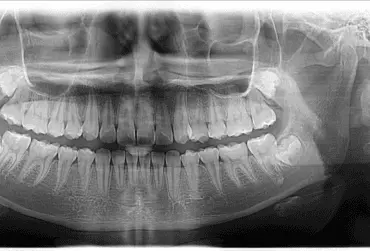

Minimalizowanie ryzyka w endodoncji, czyli procedury, które pomogą zmniejszyć ryzyko w codziennej praktyce

Leczenie endodontyczne w związku z zaawansowanym postępem technologicznym zmieniło swój wizerunek i jest uważane za skuteczne postępowanie umożliwiające utrzymanie funkcji zębów nawet w wymagających przypadkach. Zastosowanie dużych powiększeń pola zabiegowego zmieniło endodoncję w dyscyplinę wysoce skuteczną, ponieważ praktykowaną z dużą świadomością i precyzją. Lekarz stomatolog dysponuje obecnie ogromnym potencjałem i bardzo bogatym wachlarzem technik oraz materiałów wykorzystywanych podczas leczenia patologii miazgi i tkanek okołowierzchołkowych. Równocześnie ich mnogość i złożoność mogą utrudniać ogólnie praktykującym dentystom wprowadzanie zmian proceduralnych do codziennej praktyki.